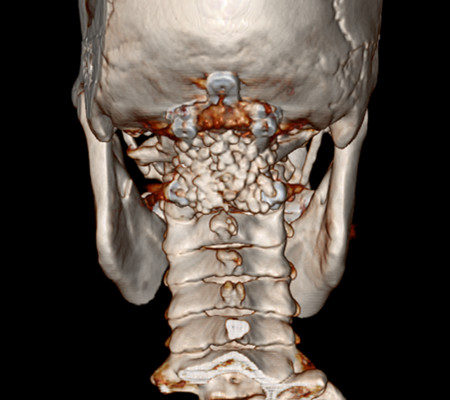

主任劉增強(qiáng)、責(zé)任總醫(yī)師巨濤等人就此病例進(jìn)行了多次討論。術(shù)前第一次運(yùn)用先進(jìn)的3D打印技術(shù)重塑了患者的寰枕部骨質(zhì)及血管,證實(shí)了患者先天性寰椎后弓缺如。經(jīng)過充分的術(shù)前準(zhǔn)備,顯微鏡下切除了下疝的小腦扁桃體,結(jié)合3D打印結(jié)果,歷時4小時完成了我院第一例后路減壓+枕頸內(nèi)固定術(shù)?;颊咝g(shù)后3天下床活動,10天出院。

寰枕畸形是指枕骨底部及第一、二頸椎先天發(fā)育異常,除以骨骼為主的發(fā)育異常外,還合并有神經(jīng)系統(tǒng)和軟組織發(fā)育異常,包括扁平顱底、顱底陷入、寰枕融合、頸椎分節(jié)不全、寰樞椎脫位、小腦扁桃體下疝畸形等。